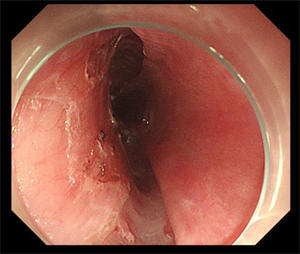

5月14日,80岁的李大爷(化名)因“再发胸闷气喘加重10天”在我院心内科住院期间,经检查,胃镜显示该患者为食管距门齿25~35cm可见两处1.5*2.0cm发红不规则糜烂,病理活检显示为鳞状上皮呈高级别上皮内瘤变(高级别上皮内瘤变相当于原位癌,也称之为食管早癌)。由于该患者曾多次因”慢阻肺、心脏瓣膜病、心功能不全、慢性房颤”住院治疗,且已有80岁高龄,若进行食管癌手术切除治疗风险大、预后生活质量会明显下降。消化内科吴斌及团队根据老人的实际情况反复研究,决定为李大爷行食管早癌消化内镜下黏膜剥离术。

术前,消化内科与呼吸与危重医学科、心血管内科、ICU、麻醉科对病例进行了充分讨论,经过精心的术前准备,在麻醉科和内镜护理团队保驾护航下,顺利完成食管早癌内镜手术。术后,呼吸与危重医学科和心血管内科协助治疗,经病理科对标本的诊断,提示患者食管早癌已治愈性切除,后期无需放疗、化疗,定期复查胃镜及胸腹部CT即可。

是通过内镜前端针对粘膜、病灶周围进行注射,在胃镜下对病变粘膜进行切割剥离,通过剥离使病灶离开胃壁或者是粘膜层。ESD术具有创伤小、不改变消化道结构、避免外科手术风险、提高术后生活质量等优点,可以帮助早期肿瘤病人达到治愈的目的。